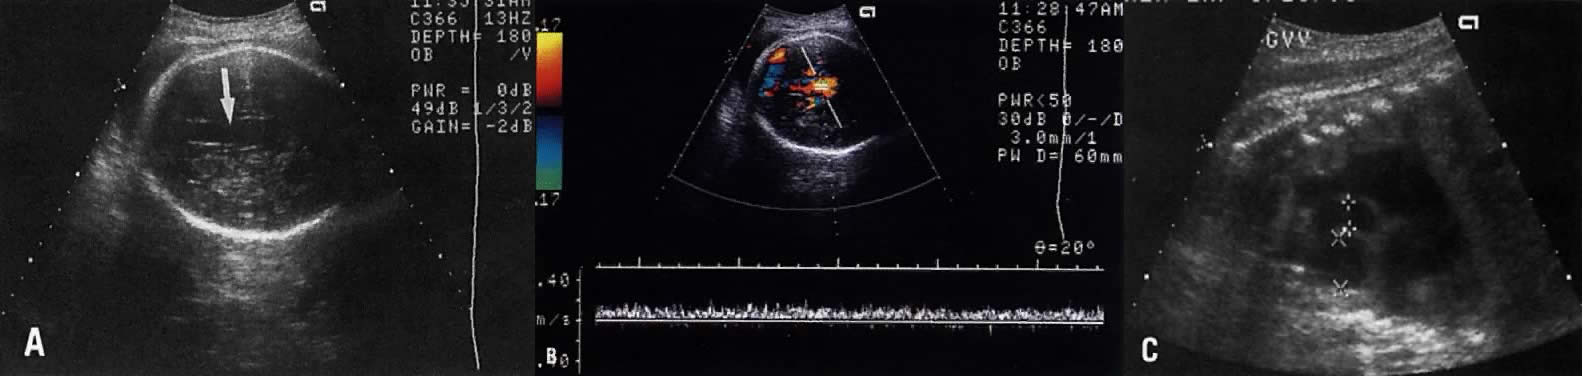

Hyperechogenicity or thickness of the ventricular walls or ventricular septum, or both, is consistent with cardiomyopathy (Fig. 4).

Fig. 4. A Cardiomyopathy in four-chamber view with very thick ventricular walls. B. Four-chamber view of the heart showing hyperechogenicity at the base of the interventricular septum (arrow), consistent with cardiomyopathy.

The ultrasonographer should obtain a number of views of the four chambers to gain adequate visualization of all these structures (Fig. 3).

Fig. 3. These echograms illustrate the need to obtain a number of four-chamber views of the heart. A. Echogram of four-chamber view showing equal-sized ventricles of normal thickness, a moderator band in the right ventricle (arrow), a normal-looking interventricular septum, and a normal septum primum. The septum secundum is not apparent. B. A second four-chamber view in same patient clearly shows septum primum and secundum, but the moderator band is not clear.

The posterior fossa shows the cerebellum and the cisterna magna (Fig. 27). Normally, the cisterna magna measures 1 to 10 mm. The differential diagnoses of an enlarged cisterna magna include trisomy 18, arachnoid cyst, and obstruction of normal CSF flow at the level of the foramina Luschka and Magendie. CSF obstruction occurs in the following conditions:

Fig. 27. A. Echogram of the fetal posterior fossa, showing (1) cerebellum (+) and (2) cystic area behind the cerebellum representing normal cisterna magna. Note that in this fetus the subcutaneous tissue posterior to the cisterna magna (X) is also thickened to 6 mm, a finding predictive of Down's syndrome. B. Fetus with massive dilation of the cisterna magna posterior to the cerebellum (+). The cerebellum is hypoplastic and the dilation secondary to Dandy-Walker malformation (see text for differential diagnosis)

In Dandy-Walker malformation, dilation of the posterior fossa results from atretic foramina Luschka and Magendie, hypoplastic cerebelli, and vermis (roof of the fourth ventricle). As a result, the dilated fourth ventricle “herniates” into the area of the cisterna magna, ultrasonically appearing as symmetrically dilated cisterna magna (see Fig. 27). In contrast, an arachnoid cyst in the posterior fossa is less symmetric.77